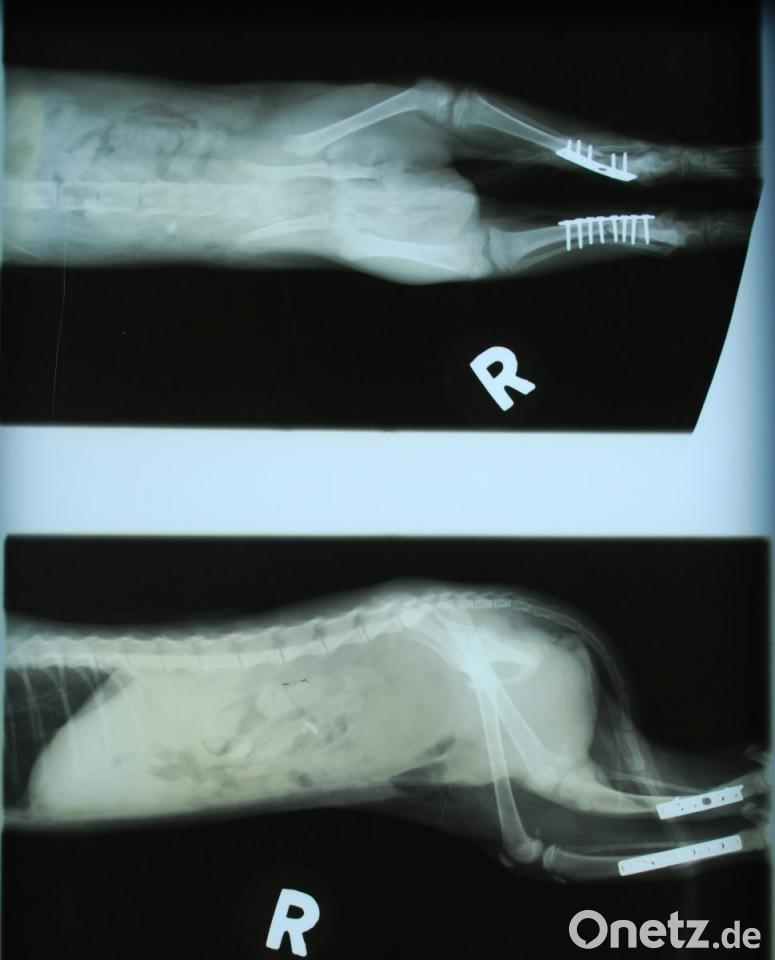

Doch der weigerte sich: "Das ist kein Grund zum Einschläfern. So etwas kann man richten, egal, was es kostet." Daraufhin hat er das Tier angenommen "und nach und nach mit großem Aufwand auf eigene Kosten operiert". Zweimal drei Stunden dauerten Bauchbruch-, Becken und Hüft-OP sowie die Verplattung beider Unterschenkel mit medizinischem Stahl. Nach ein paar Tagen konnte das Kätzchen wieder laufen, mittlerweile ist es vollkommen genesen und erkundet schon neugierig und frech seine Umwelt.